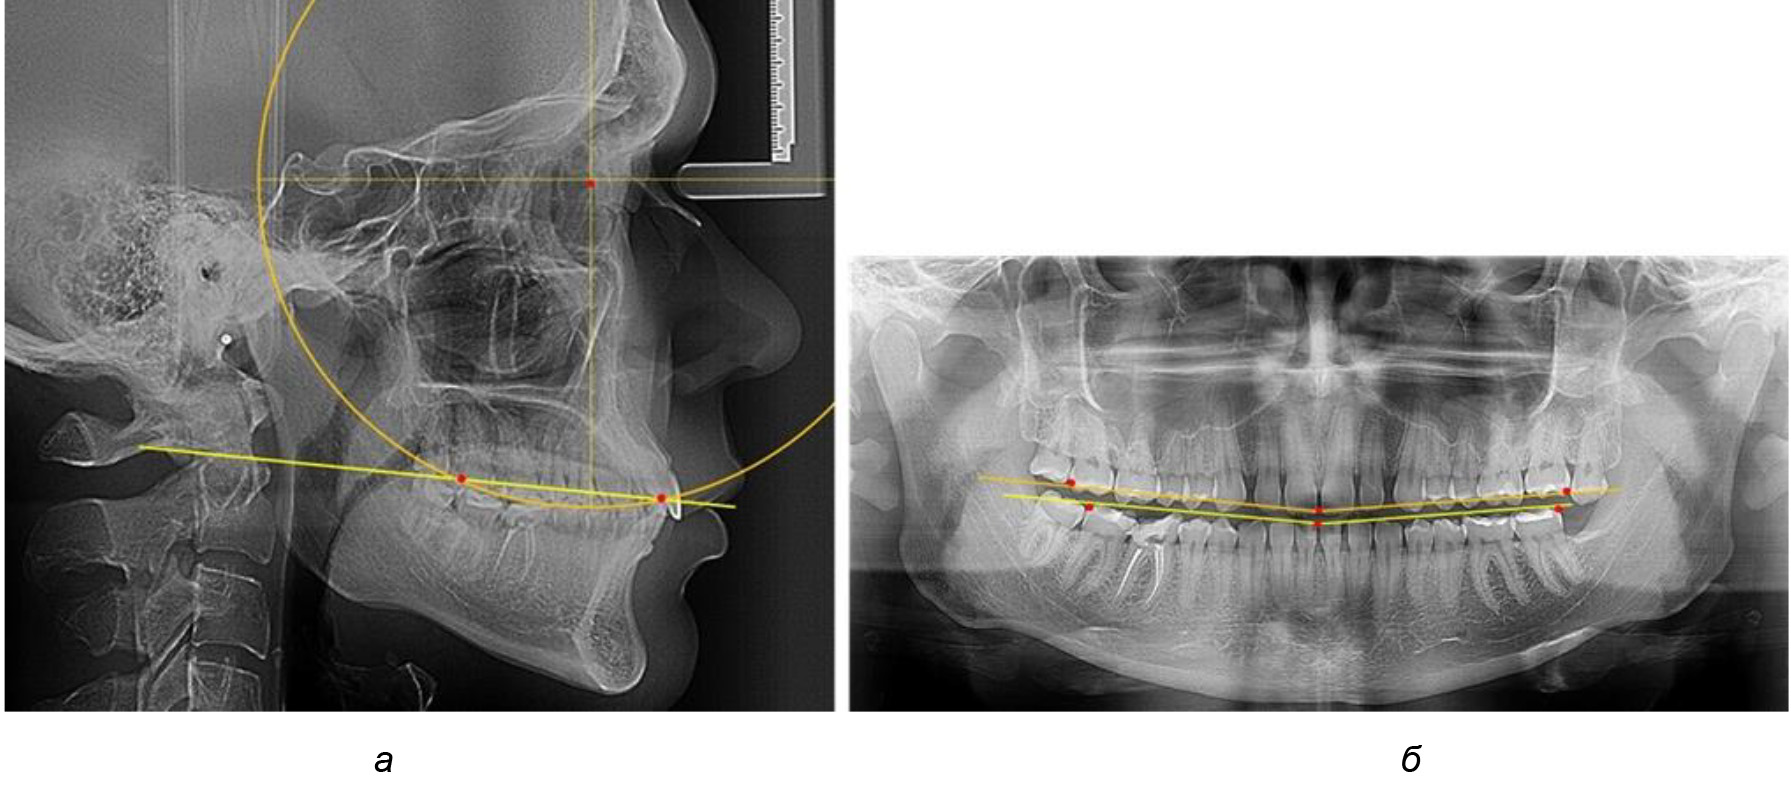

В ходе исследования установлено, что в 1-й подгруппу вошли ТРГ и ОПТГ 18 человек 1-й группы, что составило (29,03 ± 5,78) % от всех пациентов, рентгенограммы которых были проанализированы. У всех пациентов величина угла нижней челюсти была более 125° и в среднем составила (129,89 ± 3,62)° и характеризовала вертикальный тип нижней челюсти.

Анализ результатов показал, что глубина кривой Spee в среднем по подгруппе составил (4,12 ± 0,53) мм как при анализе ТРГ, так и ОПТГ.

Деление величины радиуса круга к длине окклюзионной линии составило 1,623 ± 0,02. Таким образом, для определения радиуса окружности, соответствующей кривизне окклюзионного контура боковой ТРГ, необходимо измерить расстояние между передней и задней окклюзионными точками и последующим умножением полученной величины на число Фибоначчи (рис. 2).

Рис. 2. Особенности кривой Spee на ТРГ (а) и ОПТГ (б) у людей с признаками вертикального роста